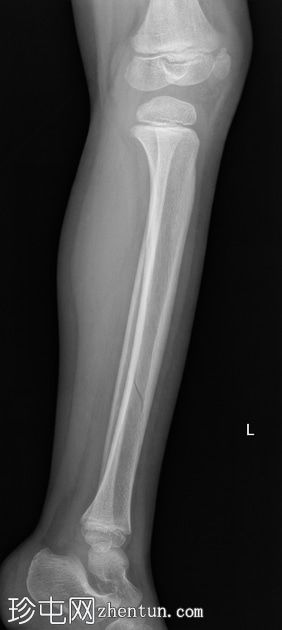

左腿外伤3天,伴

疼痛

和跛行。

年龄:5岁

性别:男

左腿及踝关节

X线片

胫骨远端骨干可见一条螺旋状透亮线,提示骨折(正位、侧位)。

应用锐化算法并放大正位片(骨折由近端向远端)和侧位片。

幼儿骨折是指幼儿因扭转(足部着地时股骨内旋)导致的胫骨中远端轻微移位的螺旋状骨折,这种情况可能发生在儿童绊倒时。患者接受了6周的石膏外固定治疗。

请注意,应用锐化骨算法并放大图像后,骨折及其范围会更加清晰可见。